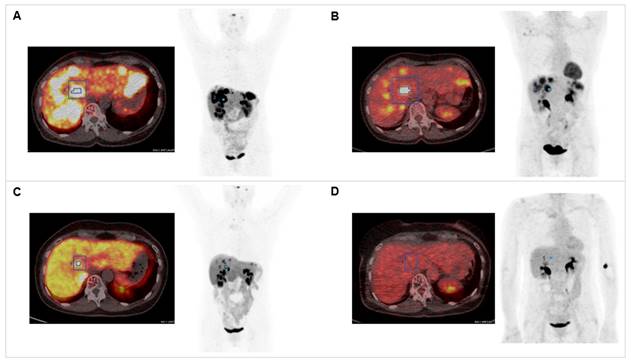

Figure 1

Combination of PRRT with CAPTEM. The patient was diagnosed with pancreatic NET (Ki-67 15%, pT3N0M0R0) following partial pancreatectomy in 2012. Dual tracer PET/CT with (A) [68Ga]Ga-DOTATOC and (B) [18F]F-FDG indicated multiple liver metastases in 2020. The combination treatment with 1500 mg/m2 capecitabine (CAP) and 200 mg/m2 temozolomide (TEM) with 177Lu[Lu]Lu-DOTATATE (accumulated activity 29.54 GBq) resulted in partial response in (C) [68Ga]Ga-DOTATOC PET/CT (SUVmax decreased from 57.43 to 24.92) and (D) complete response in 18[F]F-FDG PET/CT (SUVmax decreased from 14.51 to 4.76).